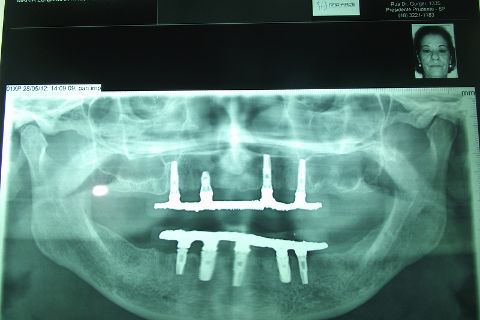

Protocolo Duplo Sendo Superior All-On-4

Caso clínico, 03 de Abr de 2014

PEDODOS EX; TOMOGRÁFIA,PANORAMICA,EX:COMPLEMENTARES

Fotos do caso